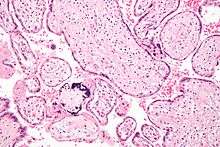

CMV infection can be demonstrated microscopically by the detection of intranuclear inclusion bodies. On H&E staining, the inclusion bodies stain dark pink and are called "owl's eye" inclusion bodies.[19]

| CMV infection of a lung pneumocyte. | |